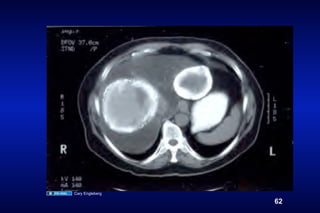

Cysticerci         Hydatid Cyst

C. Engleberg/V. Carruthers

Echinococcosis                       ingestion of

(dog) Abujoy, wikimedia commons     Cystic Hydatid Disease

Cary Engleberg

62